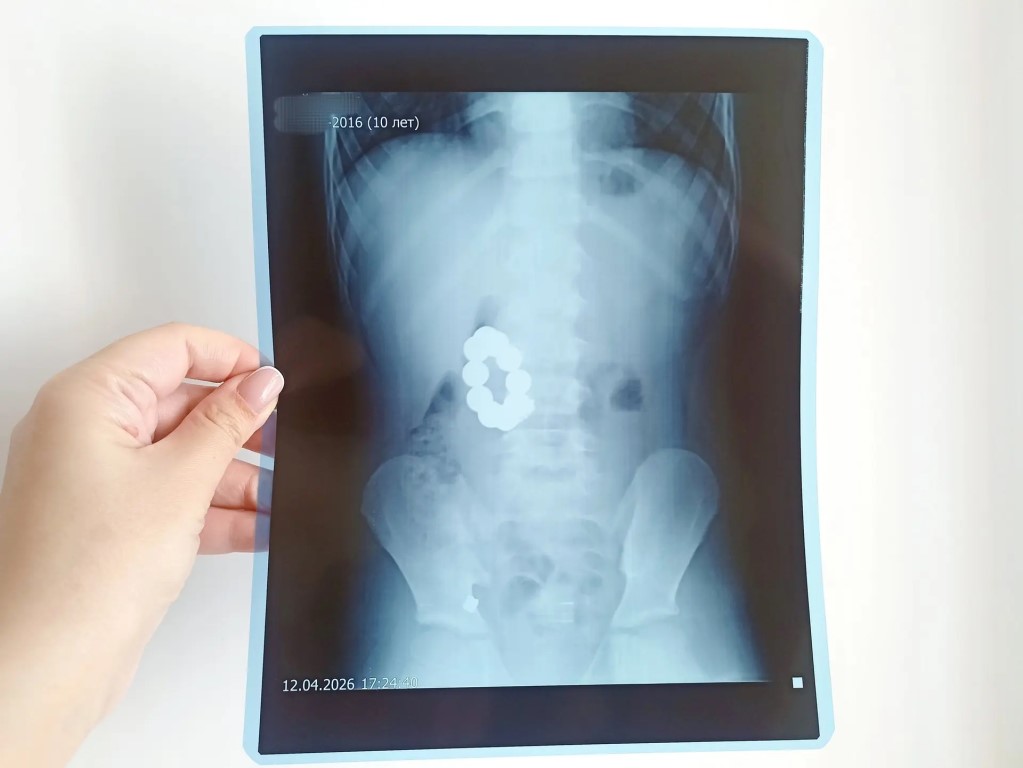

Фото Проглотившего десяток магнитов ребенка спасли в Барнауле 😧 10-летний мальчик из Крутихинского района настолько увлекся игрой с магнитными шариками, что решил проглотить манящие предметы. Через пару дней с болью в животе и рвотой его доставили в больницу в Камне-на-Оби. Оттуда пациента направили в Детскую городскую клиническую больницу № 7 Барнаула. Рентген показал, что предметы — 10 сантиметровых магнитов — сцепились между желудком и двенадцатиперстной кишкой. Помимо шариков медики обнаружили еще одно инородное тело — металлическую цепочку от брелока. «Поставив диагноз, мы сразу решили, что пойдём на лапаротомию — открытую операцию, не будем терять время на проколы. Произвели гастротомию — рассечение желудка. Сначала удалось извлечь шесть шариков и цепочку. Остальные магниты, которые находились в двенадцатиперстной кишке, достаточно долго подводили к разрезу. Их удалось достать с помощью зажимов», — вспоминает заведующая детским отделением гнойной хирургии ДКГБ № 7 Нина Мамонтова. Юному пациенту повезло получить своевременную помощь, избежав перфорации органов. В противном случае детская шалость могла привести к более серьезным последствиям. Кроме того, проглоченные магниты оказались обычными, а не неодимовыми (их дети тоже любят пробовать на вкус). Разъединить последние было бы значительно труднее, отметили врачи.